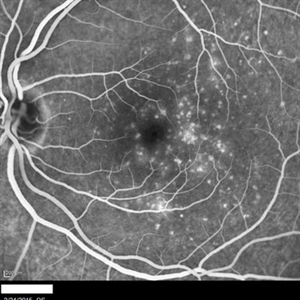

Subretinal Hemorrhage Due to SRNVM, Fluorescein Angiogram Photograph

Dec 1 2016 by James B. Soque, CRA, OCT-C, COA, FOPS

89-year-old white male with NVAMD and new subretinal hemorrhage, fluorescein angiogram, early phase, of the right eye. Currently receiving anti VEGF treatment.

Photographer: James Soque, CRA, OCT-C, COA, Island Retina, Shirley, NY

Imaging device: Topcon TRC 50 DX, with MERGE software

Condition/keywords: hemorrhage, Hot spot, neovascular age-related macular degeneration (AMD), subretinal hemorrhage, subretinal blood, wet age-related macular degeneration (wet AMD)